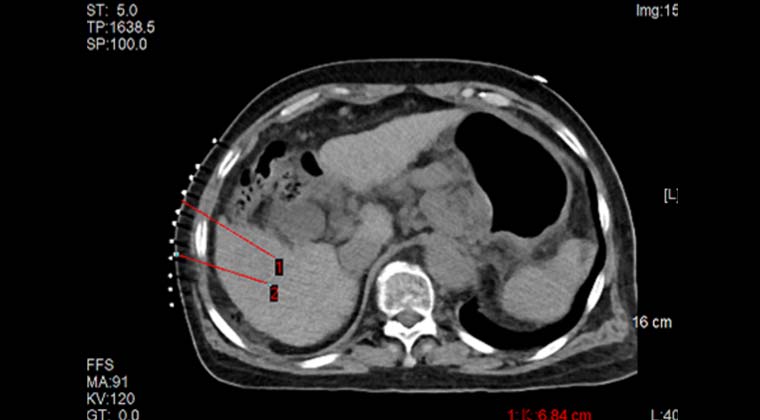

Планирование расположения электродов перед процедурой

Точная чрескожная пункция опухоли под контролем интраоперационной КТ